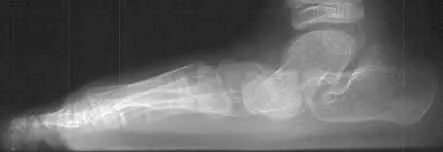

X-rays are often taken to determine the severity of the deformity. Sometimes additional imaging and other tests are ordered.